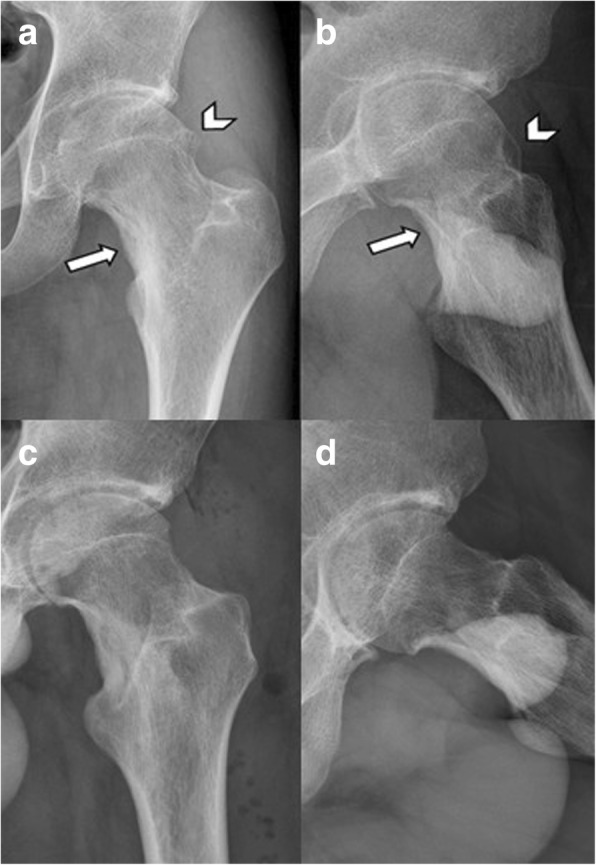

Fig. 3.

An 18-year-old male patient, who has undergone curettage and bone grafting for left femoral neck osteoid osteoma 2 years ago, presented with left proximal femur cam-type FAI. a, b Preoperative hip AP and lateral view showing the location of osteoid osteoma (arrow) and the bony bump (arrowhead). c, d Follow-up radiography at postoperative 2 years after complete removal of the cam lesion